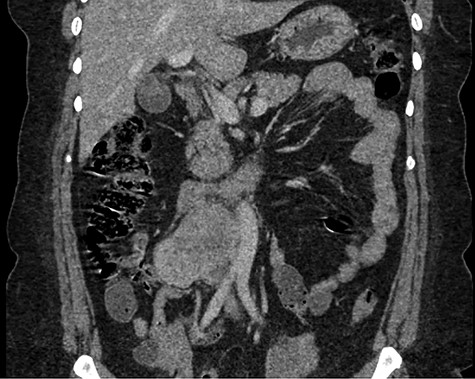

Abdominal CT demonstrating the length and location of the IVC in relation to the aorta.

The patient had a body mass index of 40, so combined with her presentation, age and gender. The presumptive diagnosis was of gallbladder pathology, which prompted an abdominal ultrasound. Ultrasound revealed a large 7.7 × 6.3 × 7.2 cm heterogenous, hypoechoic masslike lesion overlying the IVC (Fig 1). Abdominal CT was performed, which revealed an 8.9 × 7.9 × 9 cm multilobulated, heterogeneous soft tissue mass in the right hemiabdomen, encasing the IVC and partially encasing the distal abdominal aorta (Figs. 2–4). CT-guided biopsy was performed, which revealed an LMS.